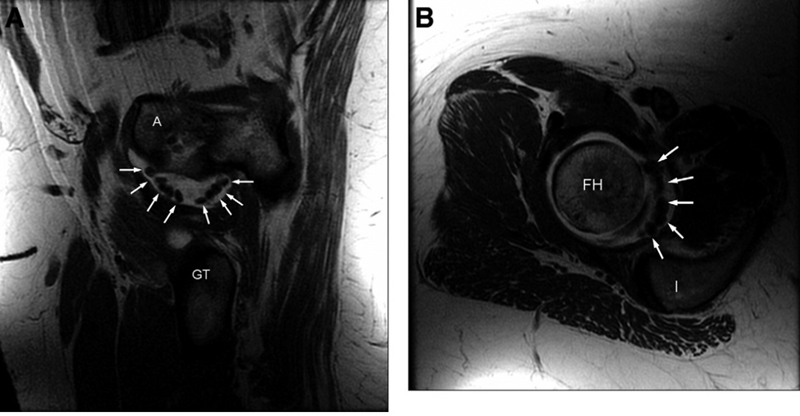

图2.滑膜软骨瘤病是髋关节内多种有症状的游离体的原因之一。使用钆造影剂或磁共振关节造影的MRl成像可用于识别软骨游离体。

(A)髋关节滑膜软骨瘤病的矢状位和(B)轴向T1加权磁共振成像扫描。箭头表示关节囊内的游离体。(A 髖臼;FH 股骨头;GT 大转子;I 坐骨。)